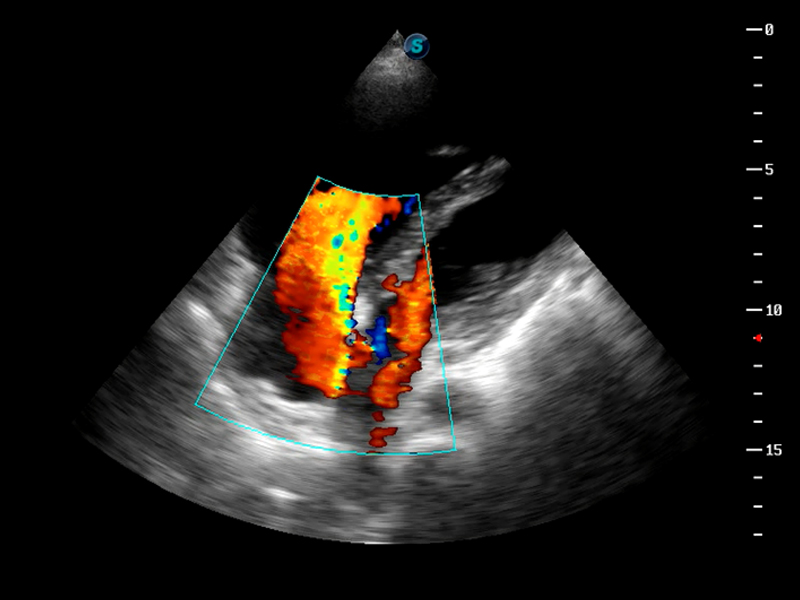

S9便携式彩色多普勒超声诊断仪是玖鼎集团研发的高端便携彩超设备,外观设计新颖、产品性能卓越。S9在便携超声领域采用了突破传统的触摸屏交互设计,并以先进的软件硬件技术和设计理念,为您带来清晰的图像质量、稳定的工作性能和便捷的操作体验。

TDI组织多普勒成像

AutoC智能血流追踪